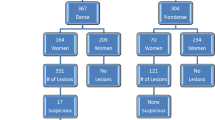

A total of 799 AB-MRI examinations were performed for the 725 women; 651 (89.8%) underwent one screening round and 74 (10.2%) underwent two screening rounds. Table 1 lists the clinicopathological findings for the 725 women. The distribution of the final BI-RADS categories was as follows: category 1 in 548 examinations (68.6%), category 2 in 154 examinations (19.3%), category 3 in 83 examinations (10.4%), and category 4 in 14 examinations (1.7%). For the women with negative AB-MRI findings, no malignancy was diagnosed for at least 1 year after screening.

Of the 83 category 3 lesions, 76 (91.6%) were followed up with AB-MRI, of which 71 were downgraded to category 1 or 2 and five were upgraded to category 4. Four of the five upgraded lesions were confirmed to be malignancies. These four malignancies (ductal carcinoma in situ (DCIS), n = 2; invasive ductal carcinoma, n = 1; mucinous carcinoma, n = 1) initially appeared as enhancing foci or nonmass enhancements on AB-MRI, with negative findings on MG or US, and exhibited interval growth during the follow-up period. The remaining one upgraded lesion was not biopsied, but it remained stable for 18 months on US and was finally categorized as a benign lesion. The seven lesions that were not followed up with AB-MRI were monitored using US or MG and exhibited no suspicious malignant findings for at least 1 year after the first AB-MRI screen.

Of the 14 category 4 lesions, 13 underwent MG-guided (n = 3) or US-guided (n = 10) biopsy, which revealed eight malignancies (invasive ductal carcinoma, n = 5; DCIS, n = 3) and five benign lesions (stromal fibrosis, n = 2; fibrocystic change, n = 1; ductal ectasia, n = 1; fibroadipose tissue, n = 1). One AB-MRI examination revealed a 2.9-cm linear nonmass enhancement that showed no corresponding abnormality on targeted US and MG. This lesion was not biopsied, and follow-up US and MG for 25 months showed negative findings.

The overall cancer detection rate with AB-MRI was 15.0 per 1000 cases [12 of 799 examinations (95% confidence interval (CI) 7.8, 26.1)], with the prevalence of invasive ductal carcinoma (median tumor size, 1.5 cm; range 0.6–2.0 cm), DCIS, and mucinous carcinoma being 50.0% (6/12), 41.7% (5/12), and 8.3% (1/12), respectively (Table 2). Seven of the 12 AB-MRI-detected lesions were mammographically and ultrasonographically occult lesions. All AB-MRI-detected cancers except one were node-negative T1 invasive cancers or DCIS. PPV1 was 12.4% (12/97) and PPV3 was 61.5% (8/13). The imaging and clinical features of the 12 malignancies detected by AB-MRI are listed in Table 2.

There were no false-negative AB-MRI findings; therefore, the sensitivity was 100% [12 of 12 (95% CI 73.5, 100%)] and specificity was 89.2% [702 of 787 (95% CI 86.8, 91.3%)]. The rates of malignancies according to the final BI-RADS category were as follows: category 1, 0% (0 of 548); category 2, 0% (0 of 154); category 3, 4.8% (4 of 83); and category 4, 57.1% (8 of 14).